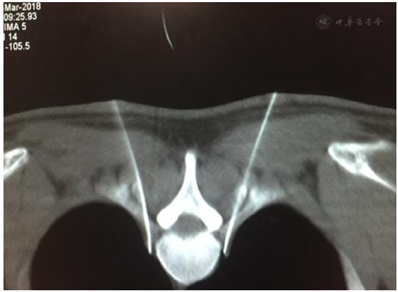

"CT引导下胸交感神经射频技术"已在嘉兴市科技局立项并取得嘉兴学院附属医院伦理委员会批准(伦理编号:LS2018-141)。术前与患者详细讲解该技术的操作流程、可能的疗效与风险,取得患者知情同意后,禁食4 h,上肢静脉留置针开放输液通道,嘱患者俯卧于CT操作台上,暴露胸背部,胸下垫软枕。监测并记录患者的血压、心率、血氧饱和度、双手掌温度和末梢灌注指数(Pulse Index,PI)。在胸4椎体(T4)对应背部皮肤上放置定位栅,用CT定位像准确定位(T3-T4)椎间隙,并以之为中心对上下两个椎体进行层厚3mm扫描,找到第4肋骨小头(R4)上方裸露的层面(椎间孔外无肋骨、关节突、椎板遮挡)作为穿刺进针层面并在该层面上设计穿刺路径:靶点为第4肋骨小头上缘。用CT自带工具软件由靶点经第4肋椎关节上缘向皮肤拉直线,与皮肤交点即为穿刺进针点,测量出拟进针深度(进针点与靶点的距离)、进针角度(穿刺针与矢状面夹角),见图1。打开CT的激光定位红线,移动CT床至所选穿刺层面,用记号笔在定位红线上标示出两侧穿刺进针点,常规消毒铺巾后,用1%利多卡因对选定穿刺点进行局部麻醉,按照拟定的进针角度和深度于CT引导下进针:双侧用长10 cm、裸露端为10 mm的7号射频针经T3-T4椎间隙进针至T4肋骨小头上缘(图2,图3),拔出针芯,沿套管插入配套电极,进行90℃ 300 s射频热凝,见视频。